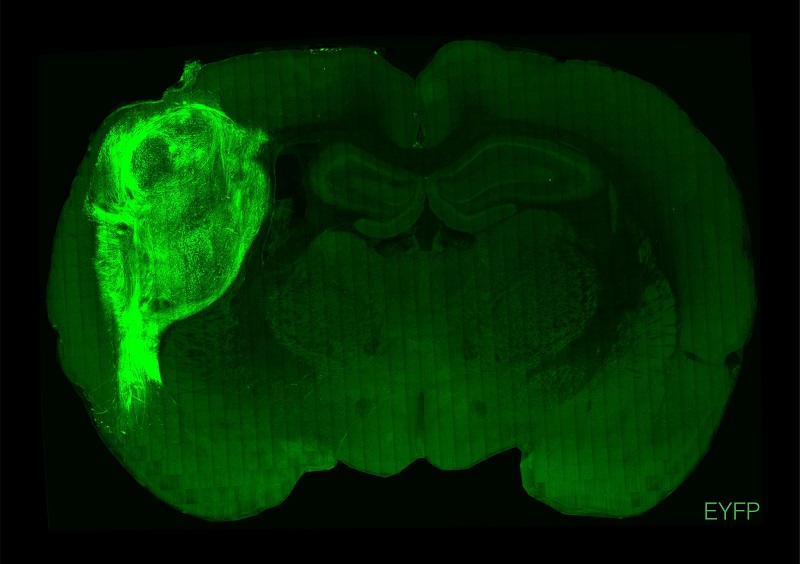

ÓÃÓ«¹âÂѰױê¼ÇµÄÈËÀàÀàÄÔÔÚ´óÊóµÄ´óÄÔÖС£¡£¡£¡£ ¡£

ͼƬȪԴ£ºË¹Ì¹¸£´óѧ